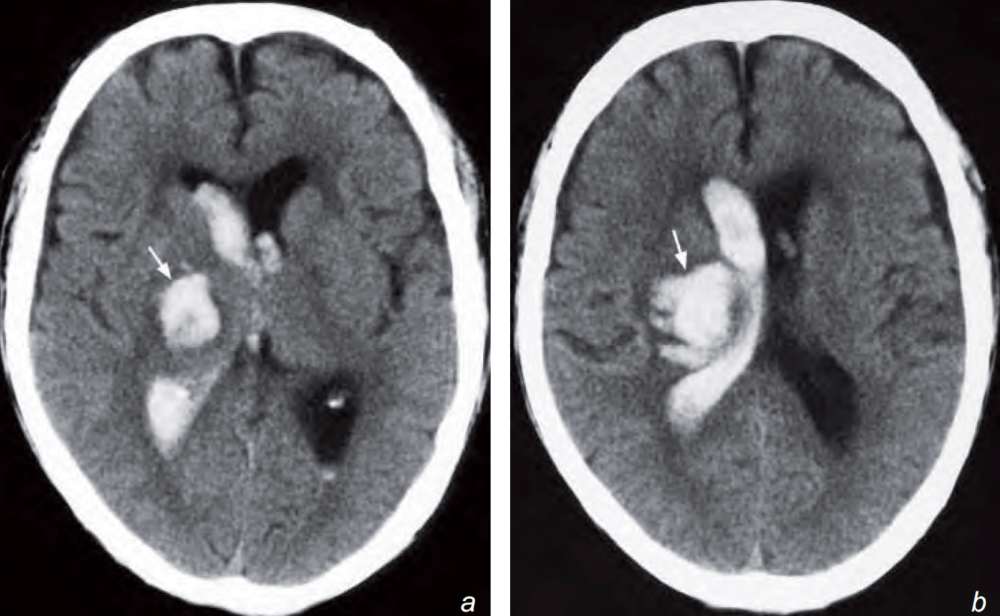

A 75-year-old man with diabetes and uncontrolled hypertension was admitted to the medical ward after suddenly becoming unconscious and developing a hemiparesis. On admission he was hypertensive with a dense left hemiplegia. An urgent CT brain was performed.

What is seen on the CT and what is the diagnosis ?